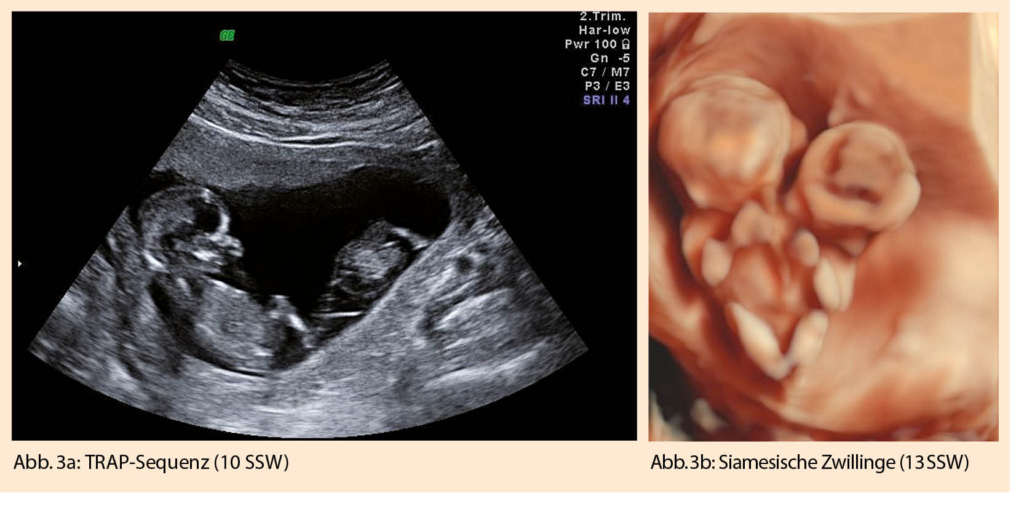

Eine weitere für monochoriale Zwillingsschwangerschaften spezifische Diagnose des ersten Trimesters ist die TRAP (twin reversed arterial perfusion)-Sequenz. Typischerweise fehlt hier bei einem Zwilling das Herz und die obere Extremität (=Akardius acranius). Eine arterio-arterielle Anastomose, vom zweiten, ‘pumpenden Zwilling’ kommend, gewährleistet die Durchblutung des Akardius acranius. Mit dem Farbdoppler lässt sich dieser umgekehrte Blutfluss gut darstellen (Abb.3 b). Die Mortalität für den pumpenden Zwilling liegt bei >50 %. Eine rechtzeitige Trennung der beiden Kreisläufe, meist mittels Lasertherapie, kann rettend sein (11).